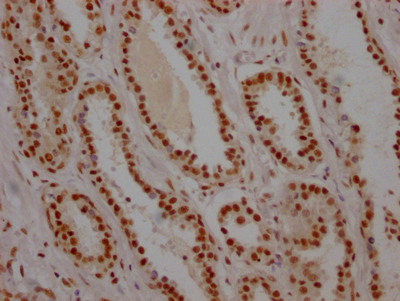

IHC image of CSB-RA215300A0HU diluted at 1:100 and staining in paraffin-embedded human breast cancer performed on a Leica BondTM system. After dewaxing and hydration, antigen retrieval was mediated by high pressure in a citrate buffer (pH 6.0). Section was blocked with 10% normal goat serum 30min at RT. Then primary antibody (1% BSA) was incubated at 4°C overnight. The primary is detected by a Goat anti-rabbit polymer IgG labeled by HRP and visualized using 0.05% DAB.